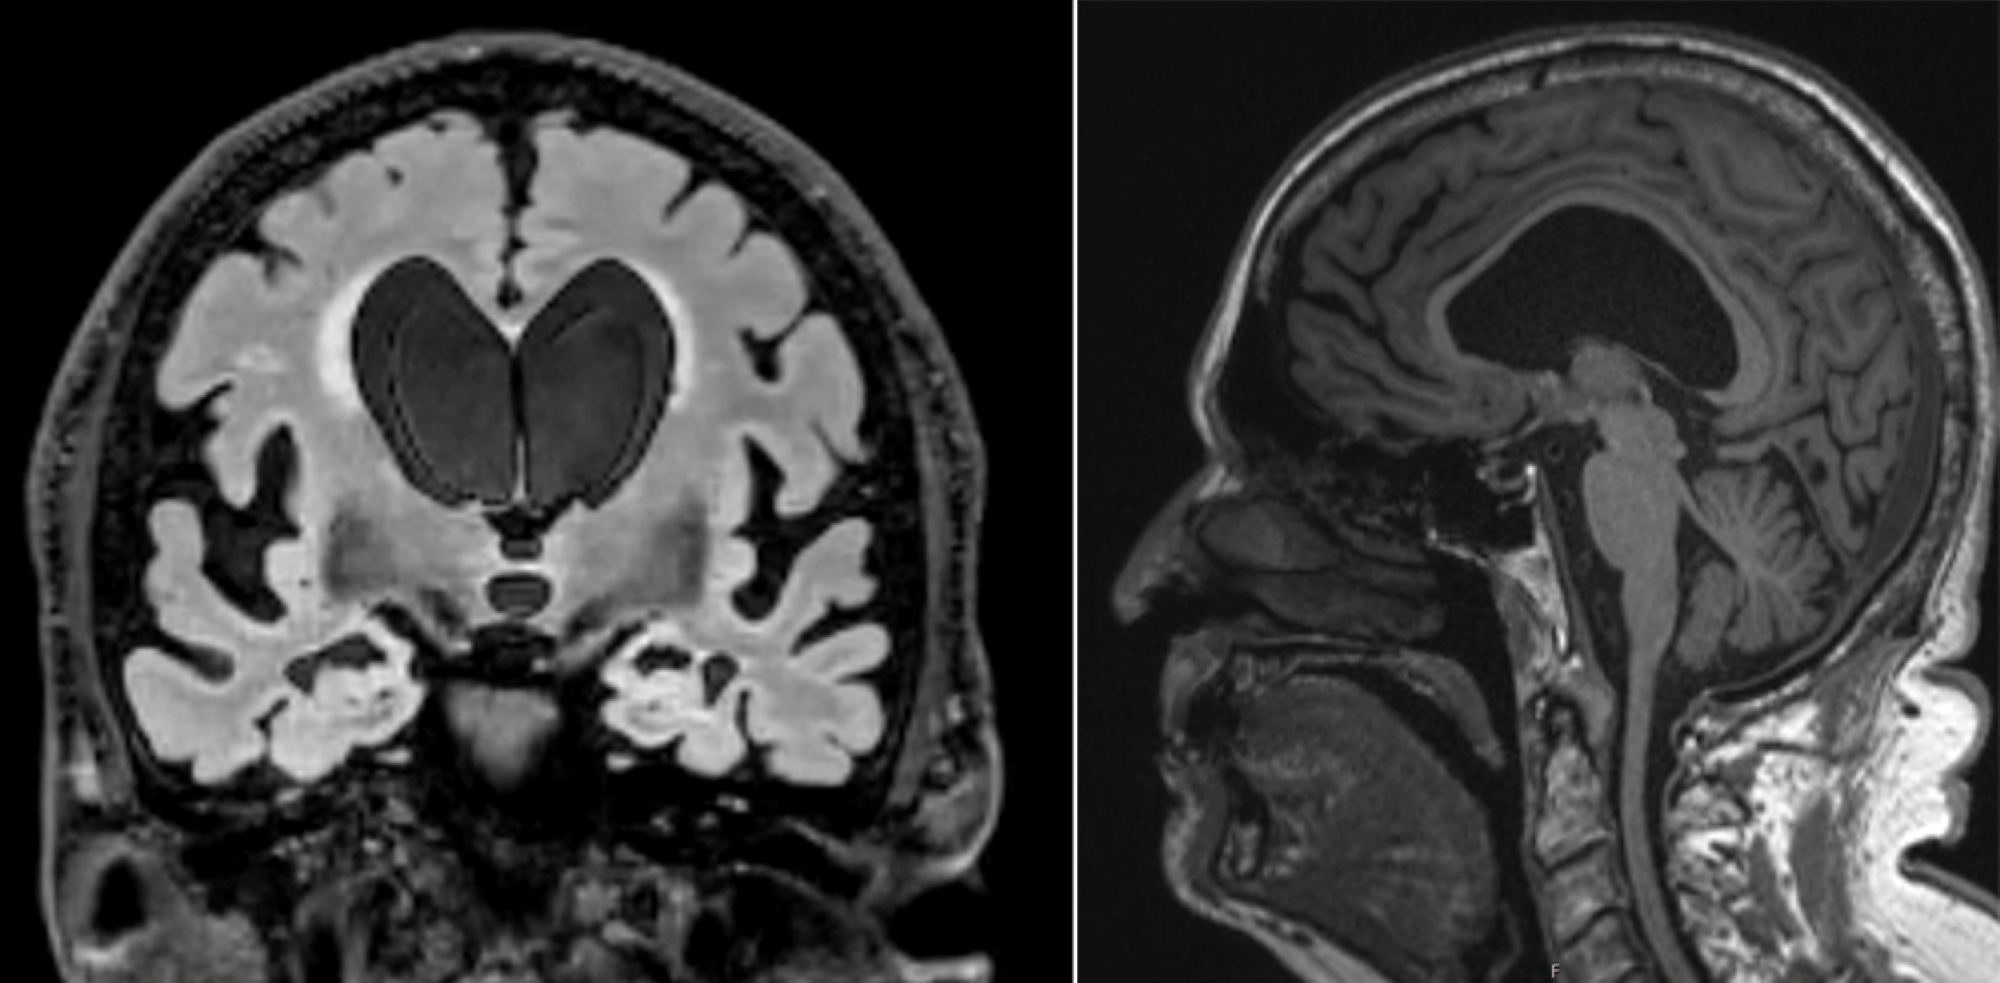

Based on his scans, the ventricles in the middle of Dick’s brain had enlarged a significant amount, likely caused by excess CSF and reduced outflow, which can disrupt communication between the brain and legs.

There also was evidence of disproportionately enlarged grooves in the brain, which happens when CSF is trapped in those spaces. On scans, this can look like brain shrinkage, which may have contributed to Dick’s earlier misdiagnosis.

MRI scans from front and side showing brain with symptoms of normal pressure hydrocephalus

Two MRI scans for Dick Nash show some of the classic signs of NPH. The scan on the left taken from the front shows large ventricles, disproportionately enlarged subarachnoid spaces at the Sylvian fissures, and narrowing of the sulci at the vertex. In the side view on the right, the ventricle fluid space is enlarged and bowing upward, with narrowing of the corpus callosum.